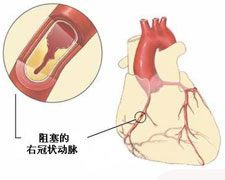

右冠狀動脈缺血

右冠狀動脈缺血本病病人與其他類型冠心病病人的不同,在於並無臨床症狀,但它又不是單純的冠狀動脈粥樣硬化,因為已有心肌缺血的客觀表現,即:心電圖、放射性核素心肌顯影,或超聲心動圖顯示心臟己受到冠狀動脈供血不足的影響。可以認為是早期的冠心病,但已不一定是早期的冠狀動脈粥樣硬化,它可能突然轉為心絞痛或心肌梗死,亦可能逐漸演變為心肌纖維化出現心臟增大,發生心力衰竭或心律失常,個別病人亦可能猝死。因此,早診斷出這類病人,可為他們創造較早期治療的機會。

3、冠狀動脈造影:

是目前冠心病診斷的“金標準”。可以明確冠狀動脈有無狹窄、狹窄的部位、程度、範圍等,並可據此指導進一步治療所應採取的措施。同時,進行左心室造影,可以對心功能進行評價。